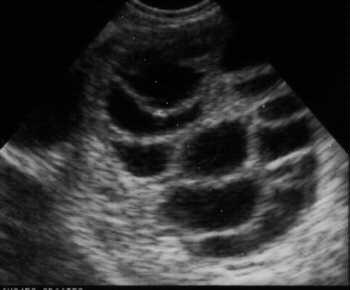

受精照片,顾名思义,就是记录受精过程的图片。它通过显微镜捕捉到精子与卵子结合的那一刻,将这个神奇瞬间永久定格。这种照片在医学领域有着重要的研究价值,但近年来,它也逐渐走进了大众的视野,成为了一种独特的艺术形式。

接下来,就是最关键的一步——拍摄。科学家们会使用高倍显微镜,将卵子和精子放大数万倍,以便捕捉到它们结合的瞬间。这个过程需要极高的技术水平和耐心,因为受精过程非常短暂,只有短短几分钟。